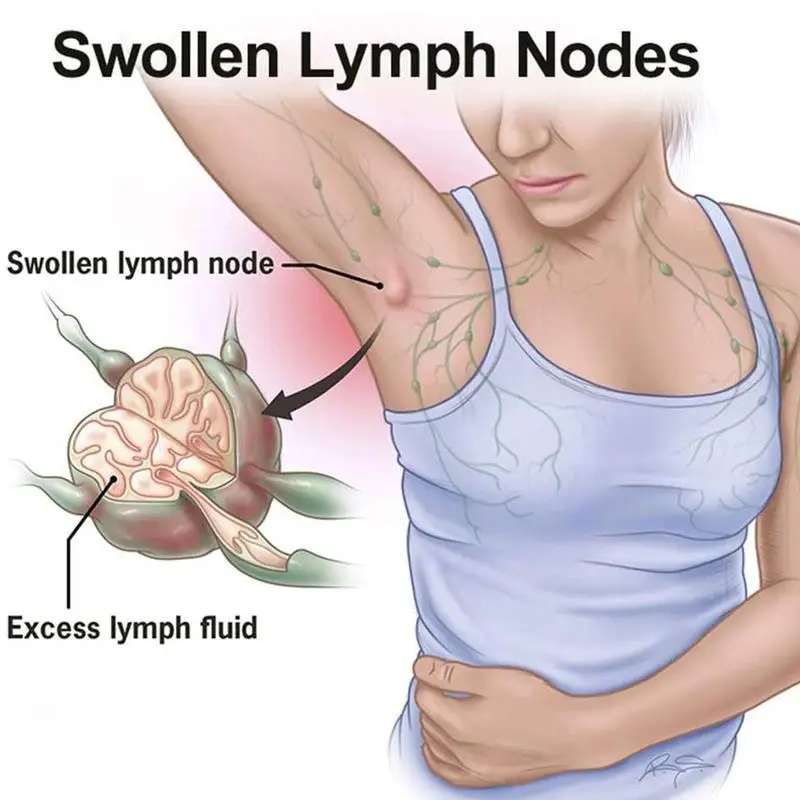

Изображения и схемы: как выглядит лимфа